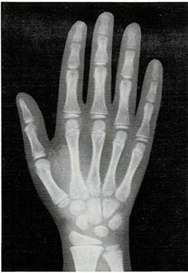

Mi madre me respondió: “Una razón de que lo encuentres blando es que sus huesos no son tan duros como los tuyos. Los niños, al nacer, tienen muy pocos huesos duros. Los huesos de su esqueleto se componen sobre todo de cartílago. Pero las células óseas trabajan sin descanso, y por ello sus huesos crecen y se endurecen muy deprisa. Tus huesos son más largos y duros que los del niño. Los huesos seguirán creciendo y se endurecerán hasta tus veinte años.

Una vez el médico me hizo una radiografía de la muñeca. Quería ver cómo crecían mis huesos. Yo le pregunté cómo era posible que mediante una foto de mis huesos pudiera saber qué le pasaba a mi esqueleto.

El médico me respondió: “Tu muñeca tiene ocho huesos. Pero no todos crecen a la vez. Los huesos de la muñeca de algunos niños crecen más deprisa o más despacio que los de otros niños. Pero los huesos de la muñeca crecen a un mismo ritmo en todos los niños sanos. Si los huesos de tu muñeca salen bien en la radiografía, quiere decir que el resto de los huesos de tu cuerpo también están bien.”

En ella ya se ven claramente los ocho huesos.